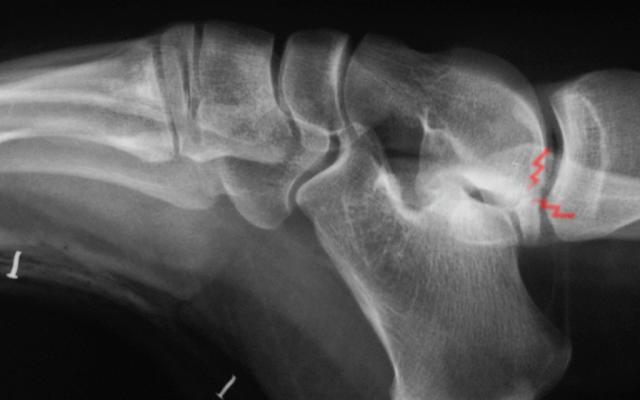

Hallux rigidus

34-year-old healthy very active female.